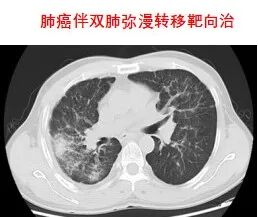

靶向治療,是在細胞分子水平,針對已經明確的致癌位點(該位點可以是腫瘤細胞內部的一個蛋白分子,也可以是一個基因片段的突變)進行靶向抗腫瘤治療。分子靶向治療具有特異性抗腫瘤作用,使腫瘤細胞特異性死亡,不會波及腫瘤周圍的正常組織,其療效增加,毒副作用明顯減少。